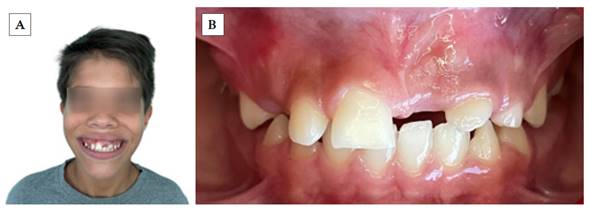

Paciente masculino de 9 años que acude a consulta con su madre. Al preguntarle el motivo de consulta, respondió: «Vengo porque no tengo un diente». La madre indica que el paciente es producto de un embarazo gemelar, sano, sin complicaciones sistémicas. Con relación a los datos sociodemográficos, comenta que son procedentes de Valencia, Estado Carabobo, Venezuela, estudiante de secundaria y habitan en casa propia con su madre, es decir, la abuela materna; además, niega cualquier tipo de alergias, consumo de medicamentos o intervenciones quirúrgicas. Se le interroga con respecto a la presencia de hábitos bucales, a lo que refiere no haber presencia. Se identifica un traumatismo dento-facial a los 18 meses con posterior avulsión dentaria, específicamente del incisivo primario superior izquierdo (UD 61). Entre los antecedentes familiares, la madre solo refiere que el padre murió por COVID-19 en el año 2020. Es importante mencionar que la madre firmó un consentimiento informado al inicio de la consulta.

Al examen clínico inicial (Figura 1), se aprecia ausencia de unidad dentaria superior; y al examen radiográfico inicial (Figura 2), la radiografía panorámica muestra una falta de erupción del incisivo central superior izquierdo permanente (UD 21), con desviación hacia el mesial de canino superior izquierdo permanente (UD 23) sin erupcionar, en íntimo contacto con la raíz del incisivo lateral izquierdo permanente (UD 22). Se puede apreciar presencia de zona radiolúcida en tercio incisal de la UD 21, presuntamente asociada a un defecto del desarrollo del esmalte, específicamente hipoplasia de esmalte. Presenta un patrón de exfoliación dental acorde a la edad en el sector inferior, etapa 8 de Nolla.

No se evidencia presencia de dientes supernumerarios ni agenesias dentales. En las imágenes axiales y frontales de la tomografía axial computarizada, puede observarse la falta de erupción de la UD 21 y su estrecha proximidad con la UD 23, así como la dilaceración radicular de la UD 22 (Figura 3). Al examen extraoral, se observa perfil facial ligeramente convexo; y al examen bucal intraoral, se aprecia overjet y overbite normales, sin apiñamiento, líneas medias dentales coincidentes con la línea media facial, clase I molar.